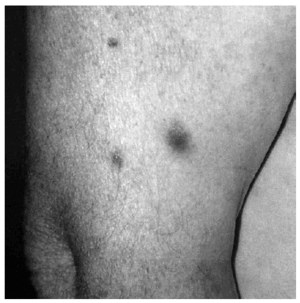

En el día +35 de quimioterapia se observaron múltiples lesiones de aproximadamente 10-12 días de evolución. Estas lesiones, papulonodulares, bien delimitadas, alguna de ellas con centro necrótico, salpicadas en tronco y miembros, eran asintomáticas y estaban infiltradas a la palpación (fig. 1). El cuadro se acompañaba de fiebre, mal estado general y debilidad muscular.

Fig. 1.--Lesiones nodulares, eritematosas, mal delimitadas, de centro necrótico en brazo.

Las lesiones cutáneas aparecen hasta en el 70% de los casos, pudiendo ser clínicamente muy variadas. Se han descrito máculas eritematosas13, nódulos15 sin o con necrosis como en nuestro caso, lesiones purpúricas o pústulas14.